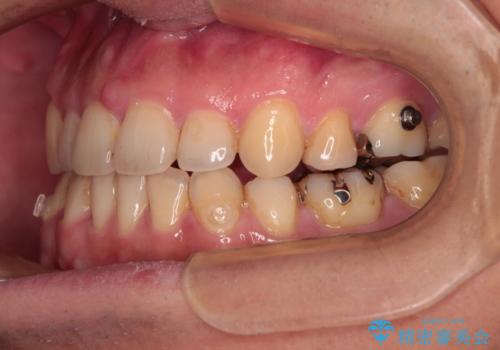

- 矯正装置

- インビザライン

- 治療期間

- 1年4ヶ月

インビザラインの特性を活用して奥歯の咬み合わせを圧下させることで、前歯のオープンバイトを改善さえることができました。